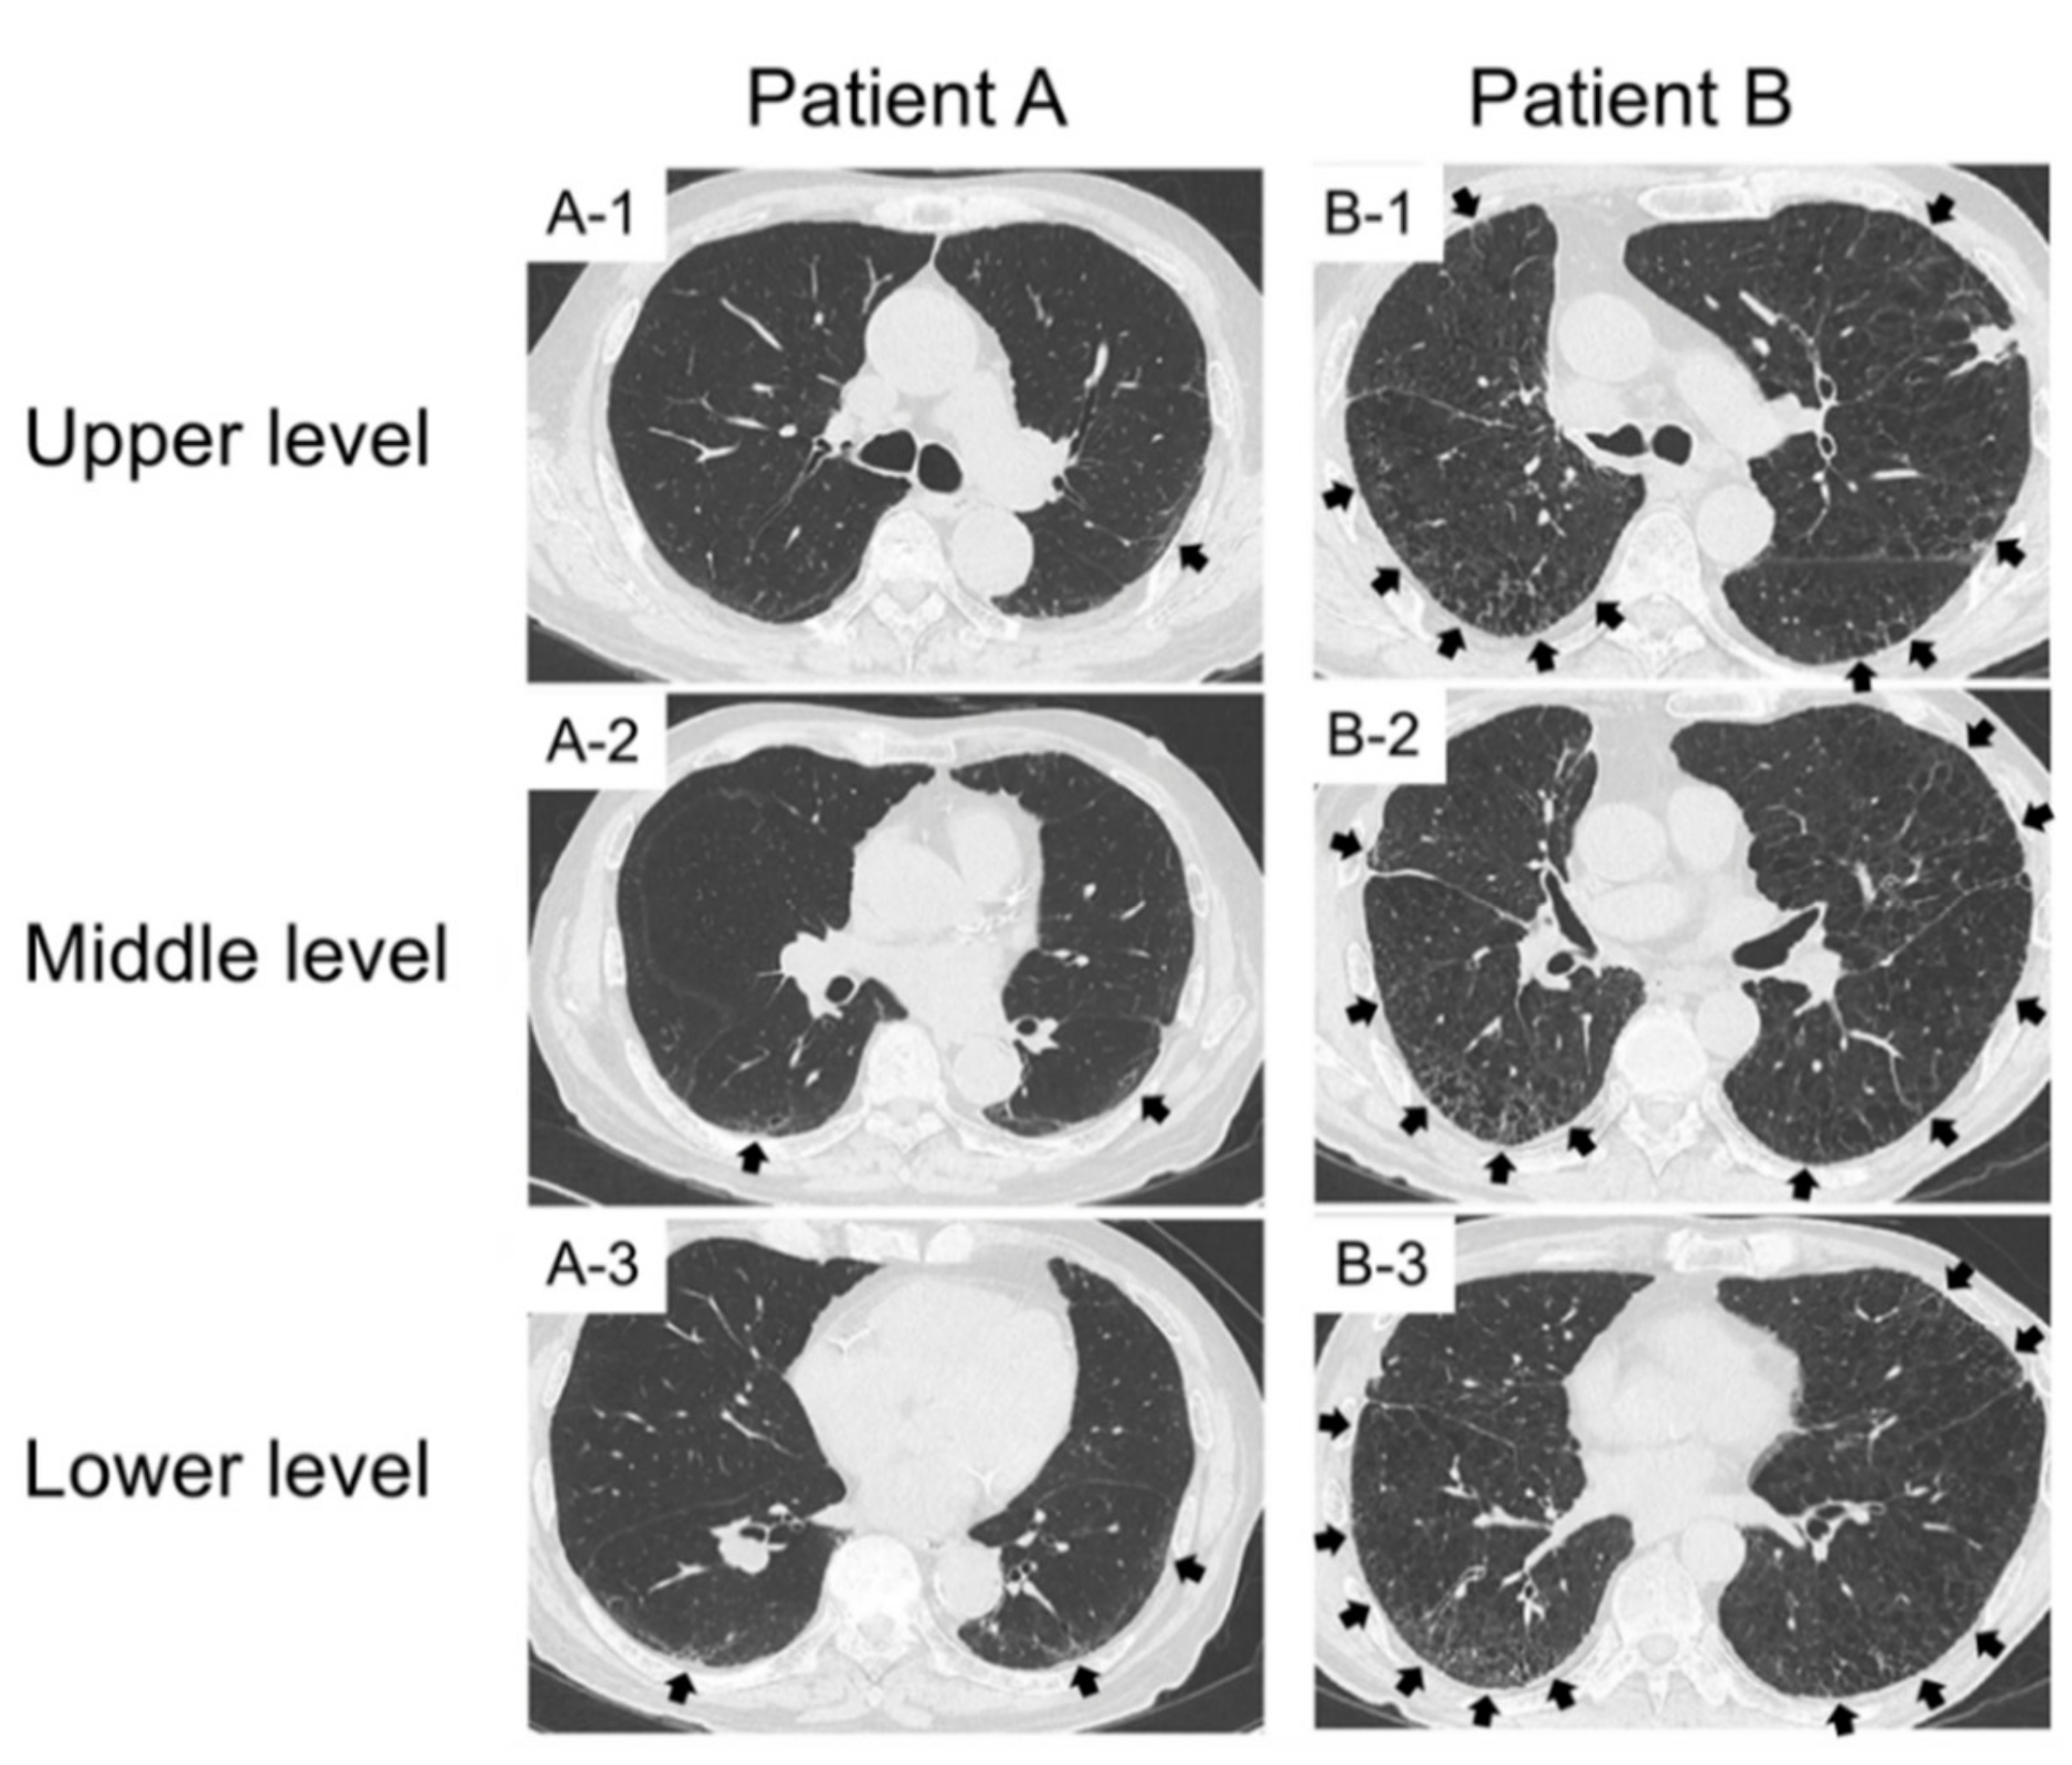

2.3. Examples of HFS and GS in Lung Cancer Patients with Pre-Existing ILD